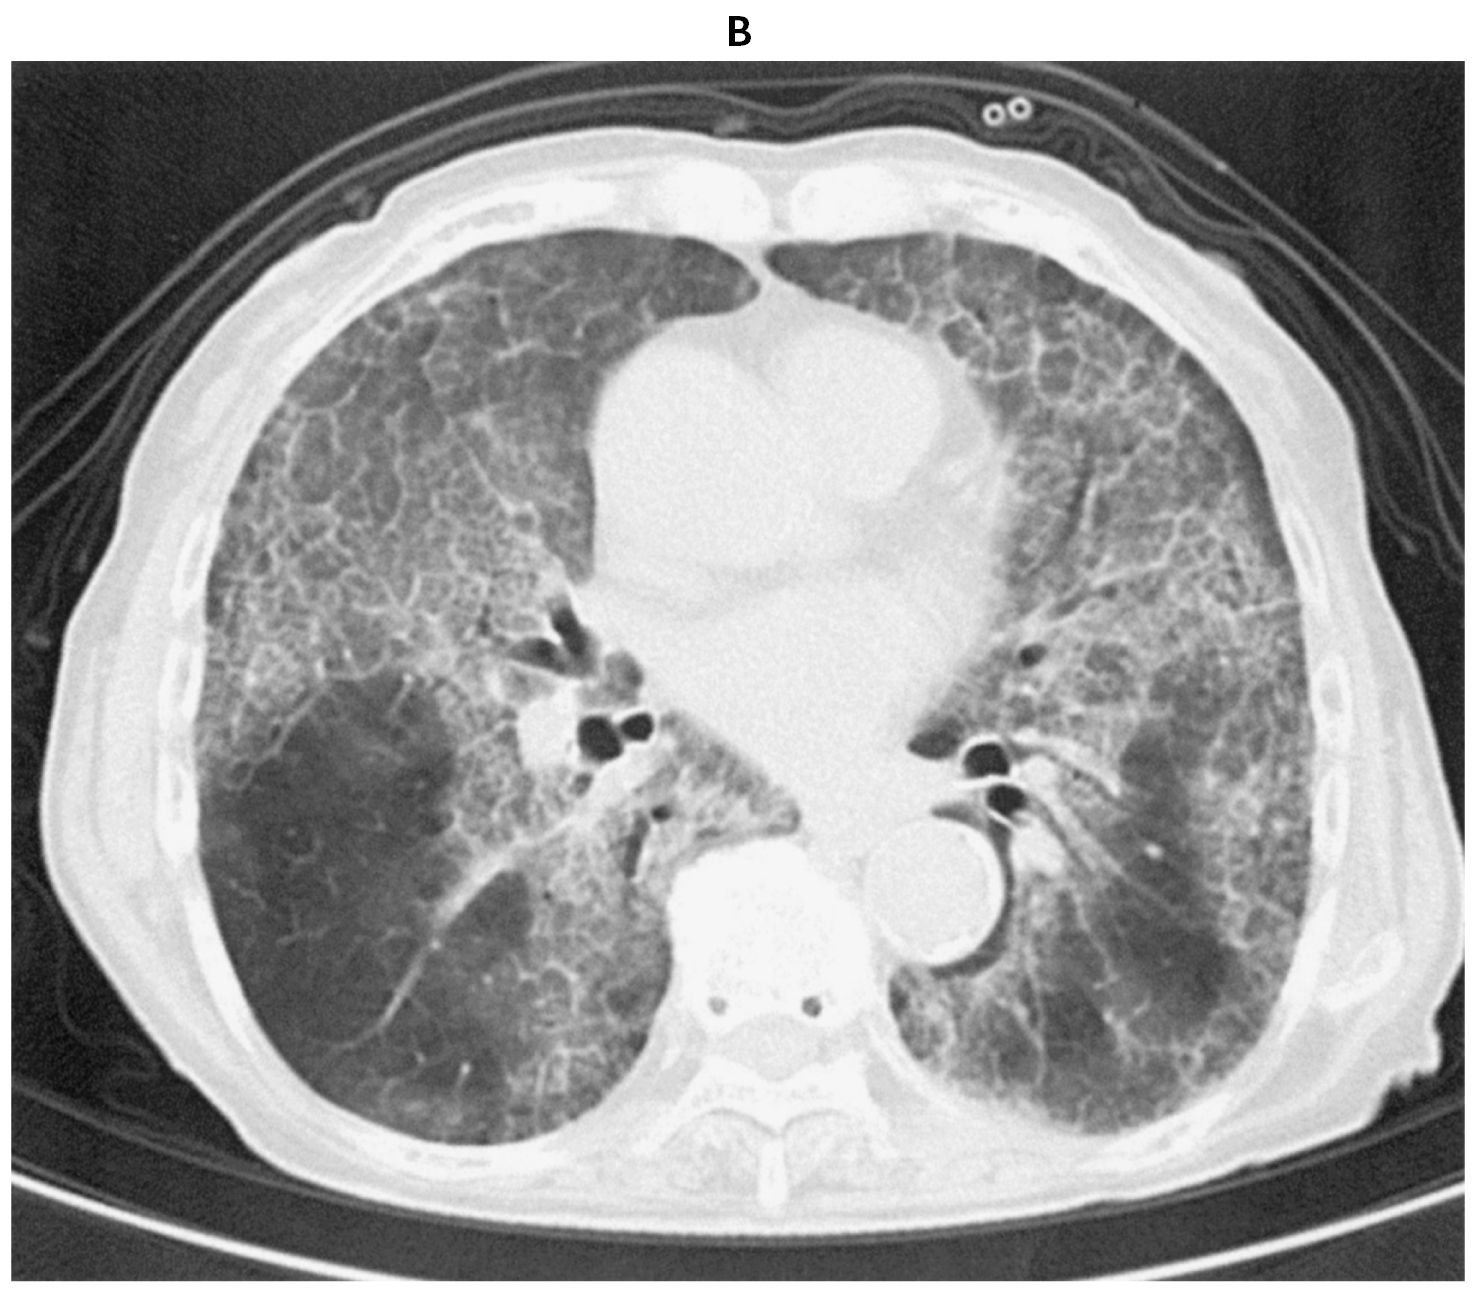

78歳の女性。労作時の息切れを主訴に来院した。6か月前から咳嗽を自覚し,1か月前から労作時の息切れが出現した。体温36.5℃。脈拍92/分,整。血圧136/90mmHg。呼吸数20/分。SpO2 92%(room air)。両側下肺野にfine cracklesを聴取する。血液所見:赤血球467万,Hb 13.8g/dL,Ht 41%,白血球3,800,血小板32万。CRP 0.1mg/dL。胸部エックス線写真(A),胸部単純CT(B)及び気管支肺胞洗浄液の写真(C)を下に示す。

無料会員登録していただくと、実際の解説をすべて見ることができます。急性の呼吸困難を主訴とする疾患としては,喉頭浮腫,気道異物,自然気胸,気管支喘息,慢性閉塞性肺疾患の急性増悪などの呼吸器疾患,心不全(急性,慢性の急性増悪),肺血栓塞栓症などの循環器疾患が代表的である。この症例では呼吸器感染症と心不全が疑われるが,胸部エックス線写真は肺炎像というよりも両心不全を示唆する所見を示している。診断:心不全(両心不全)(Nohria分類wet and warm) 選択肢考察 ×a 強い呼吸困難,胸痛などにより安静が保てない場合には,血管拡張による前負荷軽減と,交感神経抑制による心筋酸素消費量の減少を目的としてモルヒネを使用する。この症例ではモルヒネが必要となるほどの興奮状態ではない。